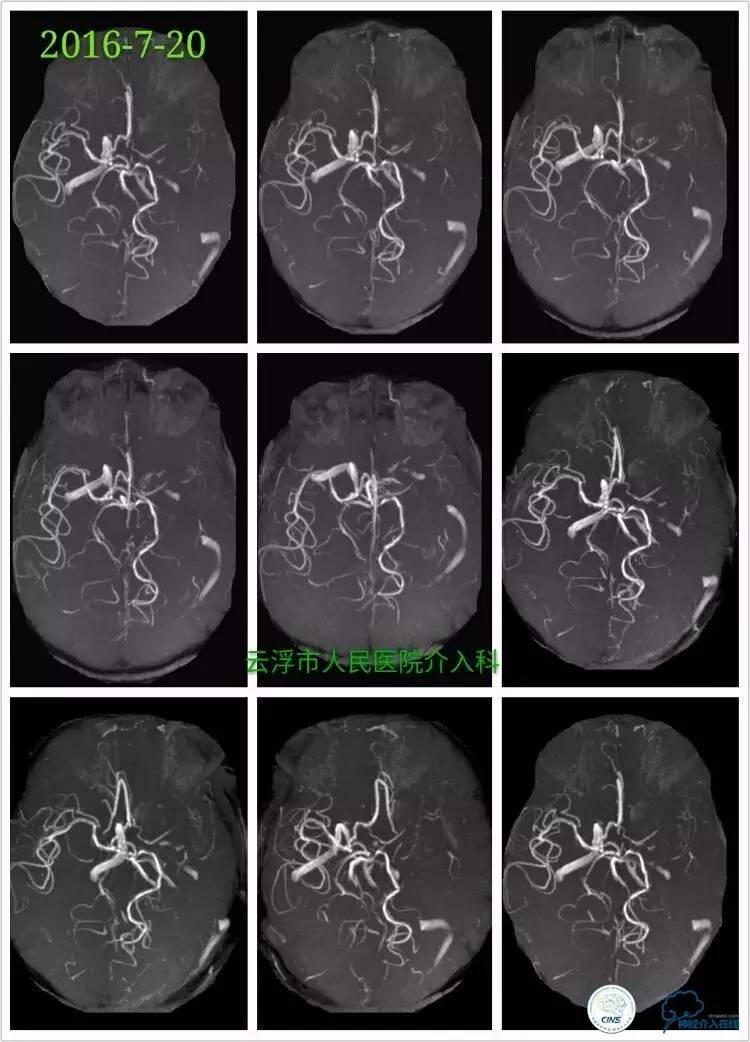

》2016-7-20

颅脑MRA检查:左侧额颞叶、基底节区、放射冠区急性脑梗塞,左侧颈内动脉颅内段重度狭窄。